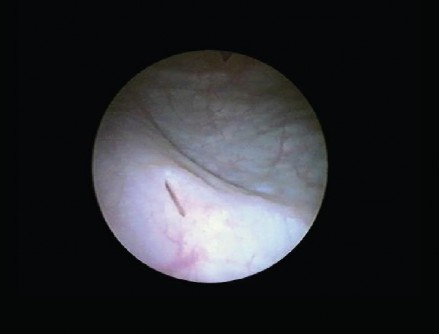

Hình 2.7. Lỗ niệu quản bên Phải